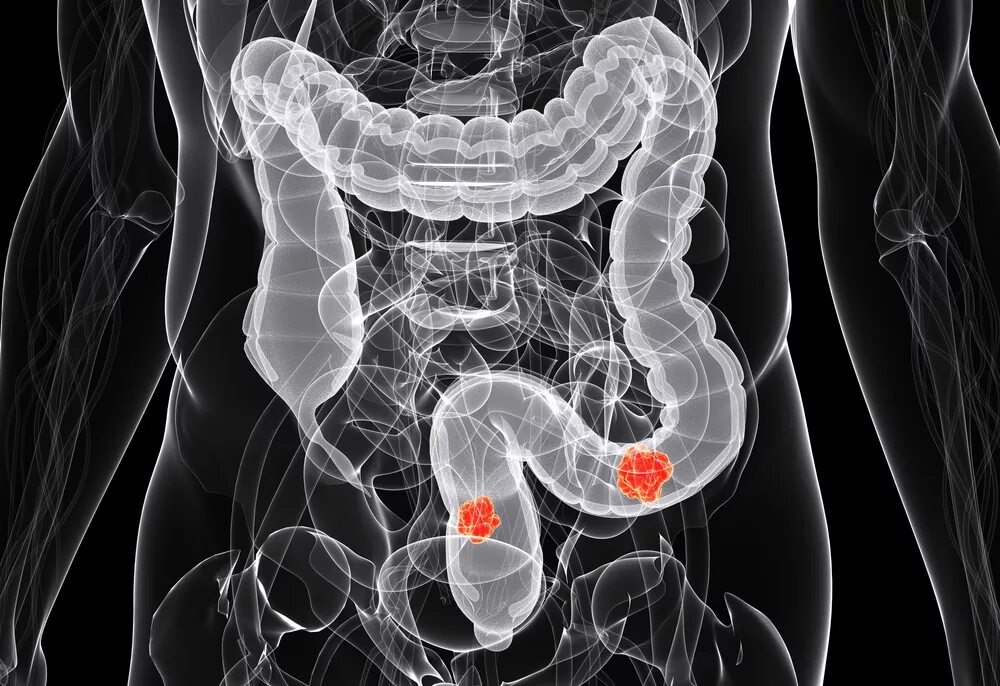

Ирригоскопия кишечника что показывает